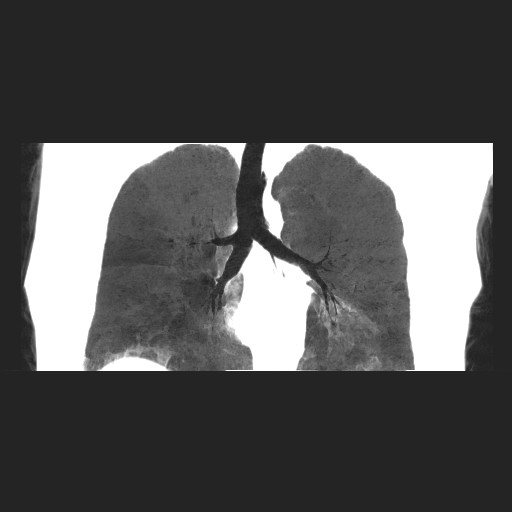

女性,62岁,长期咳嗽,既往从事工作有粉尘接触,有高血压病史,110/150mmhg,近日咳嗽加重,脸面浮肿,请大家帮看下,

1、尘肺;2、慢性支气管炎合并肺部感染;3、心影增大(左房、左室大),考虑高血压性心脏病。

慢支并肺部炎症;右肺结核球?主肺动脉、右肺动脉影不宽,右心室不大,不支持肺心病;无心包积液。

1)慢性支气管炎并肺部感染、肺气肿。2)肺间质纤维化。